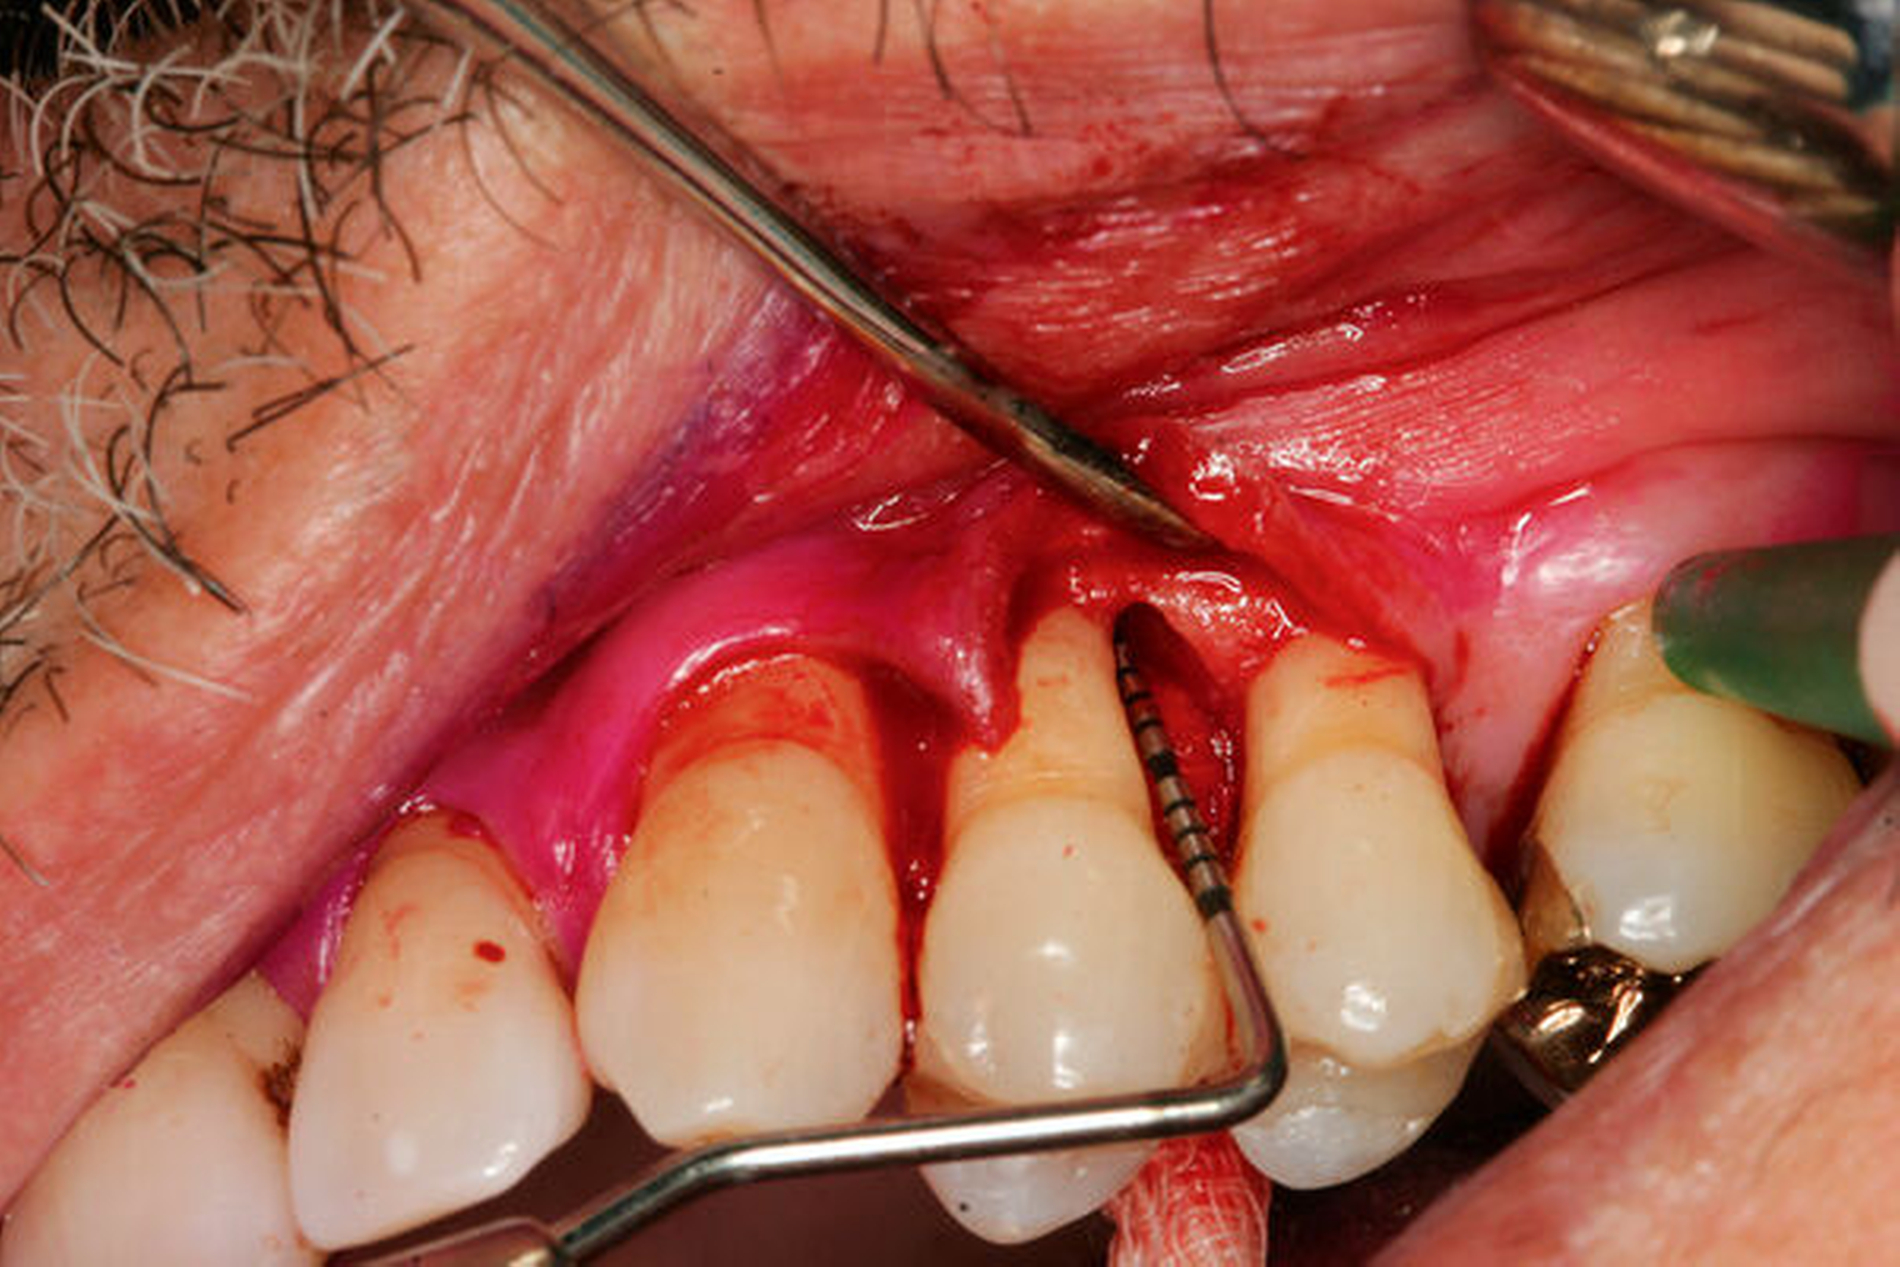

Den evidenzbasierten Empfehlungen der klinischen Leitlinie zu regenerativer Therapie von Knochentaschen (Abbildung 4) liegen 22 RCTs mit 1.182 Zähnen bei 1.000 Patienten zugrunde [Nibali et al., 2020]. In der Mehrzahl der Studien führte die regenerative Parodontaltherapie zu besseren parodontalen Parametern (höherer CAL-Gewinn und flachere Taschen) im Vergleich zur Instrumentierung unter Sicht (Zugangslappenoperation). Für den CAL-Gewinn wurde ein zusätzlicher Nutzen von durchschnittlich 1,34 mm (95 Prozent-KI: [0,95; 1,73]) und für die TST-Reduktion von 1,20 mm (95 Prozent-KI: [0,85; 1,55]) beobachtet. Das stellt eine Verbesserung von 80 Prozent (95 Prozent-KI: [60 Prozent; 100 Prozent]) im Vergleich zu den Kontrollgruppen dar. Ein mittlerer Unterschied in dieser Größenordnung wird als klinisch relevant erachtet, da damit das Risiko des Zahnverlusts reduziert wird. Beobachtungsstudien und experimentelle Studien, die sich mit Zahnüberlebensraten von 3 bis 20 Jahren beschäftigt haben, zeigten bessere Überlebensraten von Zähnen mit parodontaler Regeneration in regelmäßiger unterstützender Parodontaltherapie [Stavropoulos et al., 2021].

Dieser Empfehlung liegen 20 RCTs mit 972 Patienten zugrunde [Nibali et al., 2020]. Im Vergleich zur Zugangslappenoperation wurde ein zusätzlicher Nutzen für den CAL-Gewinn von durchschnittlich 1,27 mm (95 Prozent-KI: [0,79; 1,74]; Verbesserung von 77 Prozent) für EMD (Enamel Matrix Derivative, Schmelz-Matrix-Proteine) (Abbildung 4) und von 1,43 mm (95 Prozent-KI: [0,76; 2,22]; Verbesserung von 86 Prozent) für GTR (Guided Tissue Regeneration, gesteuerte Geweberegeneration) beschrieben. Die Kombination von Membranen und Knochenersatzmaterial resultierte in einem CAL-Gewinn von 1,5 mm (95 Prozent-KI: [0,66; 2,34]; Verbesserung von 90 Prozent) im Vergleich zur Zugangslappenoperation. Der Vergleich von EMD zu GTR zeigte keinen statistisch signifikanten Unterschied hinsichtlich CAL-Gewinn [Nibali et al., 2020].

Was ist das adäquate Lappendesign für die regenerative Therapie von Resttaschen im Bereich von Knochentaschen?

Dieser Empfehlung liegen zwei systematische Übersichtsarbeiten zugrunde [Graziani et al., 2012; Nibali et al., 2020]. Durch einen Papillenerhaltungslappen lassen sich höhere CAL-Gewinne und TST-Reduktionen erreichen. Im Vergleich zur Instrumentierung unter Sicht (Zugangslappenoperation) führt diese Technik zu geringeren postoperativen Rezessionen. Die erhöhte Komplexität dieser Methode bedarf allerdings zusätzlichen Trainings. (Abbildung 4).